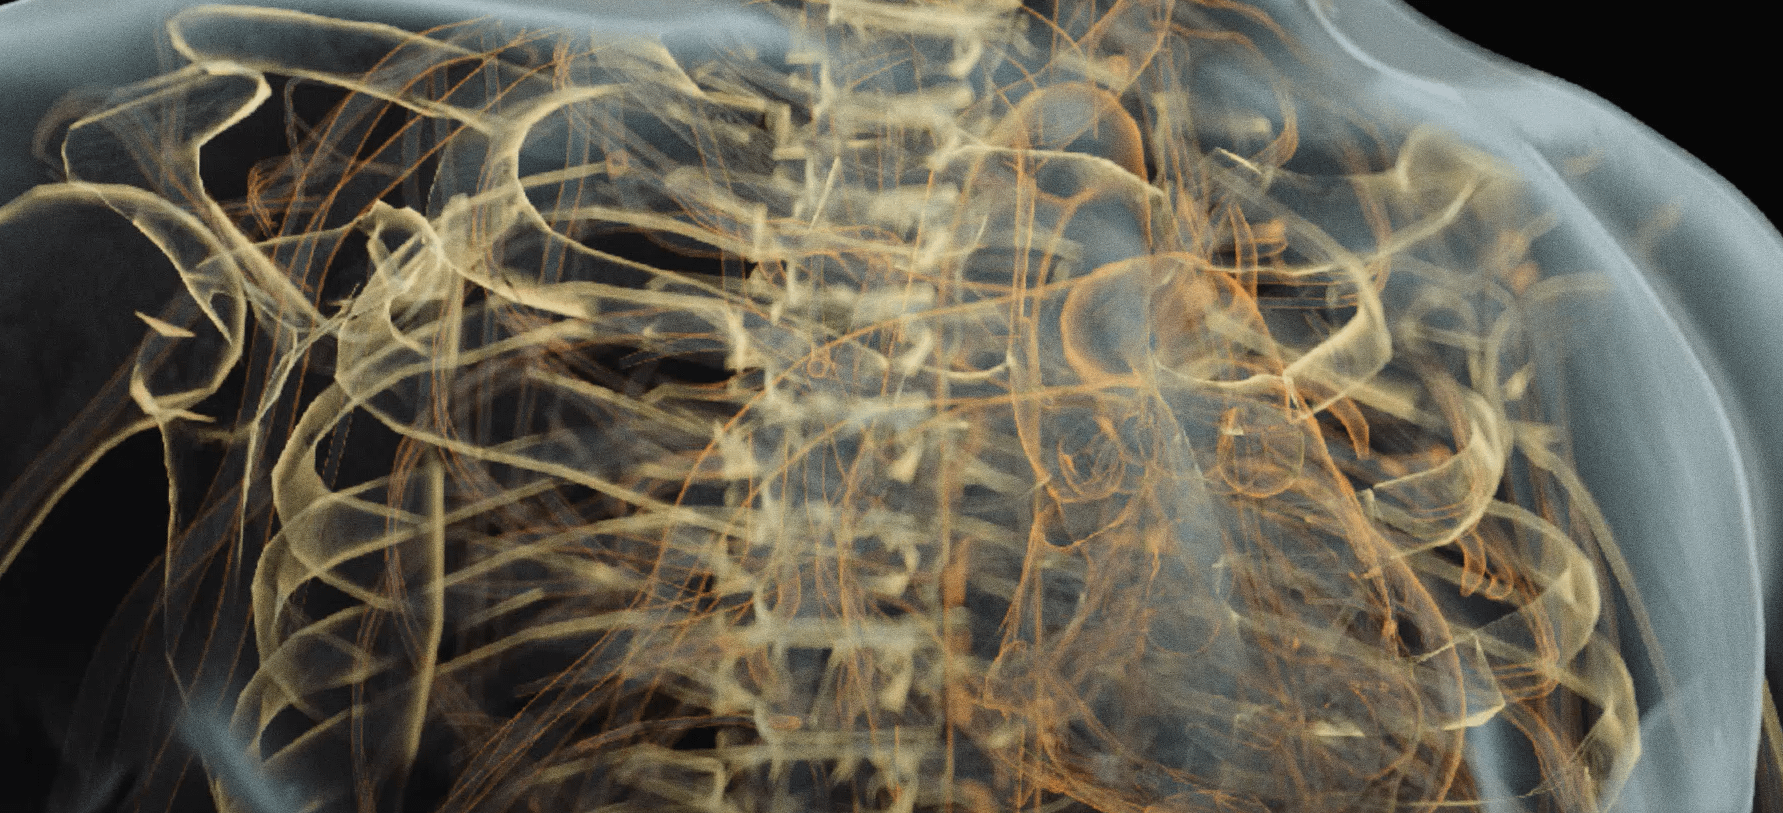

The benefits include better spatial resolution, improved contrast – in many applications – lower radiation dose. Photon counting also enables the separating tissues, or combined, to form ‘color’ images – after the acquisition. The added energy domain information allows sophisticated post-processing algorithms which can aid the user to focus on the areas of clinical interest.

Photon counting based computed tomography (PC-CT) is the latest implementation of photon counting technology and its advantages are already evident. The enhanced contrast to noise ratio of photon counting detectors allows imaging at low dose. The 3D images also reveal a range of detailed information that might not have been seen previously because of the reduction in noise.

Patients can be scanned in 8 seconds but with less dose because of the sensitivity of Varex photon counting X-ray detectors. Our detectors are optimized for scanning applications with the built-in digital time-delay summation (TDS) mode. The high spatial resolution offers clinicians additional, high-quality information that could aid in comprehensive and detailed patient assessment.

Dual energy and multi-energy imaging allow the clinician the opportunity to look more closely at bone composition and density, important parameters for the diagnosis of skeletal diseases.

The dual energy function provides three views, e.g. one of soft tissue, the other of bone structures as well as the conventional absorption image, as the energy of each photon can be correctly measured and registered. This advanced feature could be of value to, for example, lung examinations.